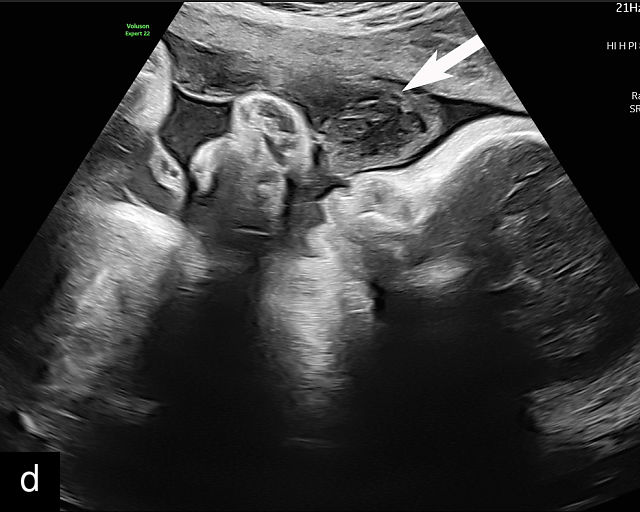

6

Placenta accreta spectrum. (a,b) Sagittal transabdominal grayscale ultrasound of the lower uterus and cervix demonstrating placenta previa accreta, with the placenta (p) containing prominent irregular hypoechoic lacunae. There is absence of the myometrium at the bladder (b) interface (arrows) c, cervix. (c) Sagittal transabdominal color Doppler ultrasound of the lower uterus and cervix demonstrating placenta previa accreta, with increased vascularity of the lower uterus and the myometrial bladder interface. (d) Transvaginal ultrasound of placenta previa accreta showing multiple lacunae involving the cervix with no clear demarcation between the placenta and the cervix. (e) Transvaginal ultrasound of placenta previa accreta showing multiple large irregular lacunae involving the cervix with no clear demarcation between the placenta (p) and the cervix. The placenta has a ‘moth-eaten’ appearance. There is loss of myometrium (arrows). (f) Transvaginal ultrasound of placenta previa accreta without and with color flow Doppler showing multiple large irregular lacunae. The placenta has a ‘moth-eaten’ appearance. There is hypervascularity of the myometrial interface. (g) Transvaginal ultrasound of placenta previa accreta showing multiple lacunae involving the cervix with no clear demarcation between the placenta and the cervix. (h) Transvaginal ultrasound of placenta previa accreta with color flow Doppler showing hypervascularity of the myometrial interface and irregularity of the bladder wall. b, bladder; p, placenta. (i) Transabdominal grayscale ultrasound of cesarean scar pregnancy. The uterine fundus (f) is empty (arrowhead). The gestational sac (arrow) is located in the lower uterus, anterior to the uterine canal, and lies above the cervix (c). b, bladder. (j) Transvaginal grayscale ultrasound image of cesarean scar pregnancy showing the empty fundus (f) and the normal cervix (c). The gestational sac lies below the fundus, above the cervix and anterior to the uterine cavity. (k) Transvaginal grayscale ultrasound image of cesarean scar pregnancy showing the empty cavity (arrowheads) of the uterine fundus (f), and the normal cervix (c). The gestational sac lies below the fundus, above the cervix and anterior to the uterine cavity (arrow).

Several characteristic sonographic findings are associated with PAS.90,95,96,97 These include placental lacunae, which appear as hypoechoic, irregular spaces within the placenta with high-velocity turbulent flow on color Doppler.16,50 Other features include obliteration of the retroplacental clear space, thinning of the myometrium in the lower uterine segment, irregularity and hypervascularity of the myometrial–bladder interface, and placental bulging into the bladder (Figure 6a–h).90,96,98,99